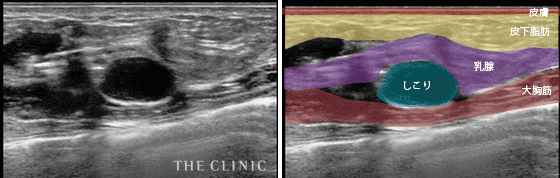

- 乳腺組織内にしこりができてしまった症例